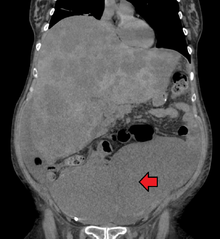

Appearance of the inside of the colon showing one invasive colorectal carcinoma (the crater-like, reddish, irregularly shaped tumor)

Gross appearance of a colectomy specimen containing two adenomatous polyps (the brownish oval tumors above the labels, attached to the normal beige lining by a stalk) and one invasive colorectal carcinoma (the crater-like, reddish, irregularly shaped tumor located above the label)

Endoscopic image of colon cancer identified in sigmoid colon on screening colonoscopy in the setting of Crohn's disease

PET/CT of a staging exam of colon carcinoma. Besides the primary tumor a lot of lesions can be seen. On cursor position: lung nodule.